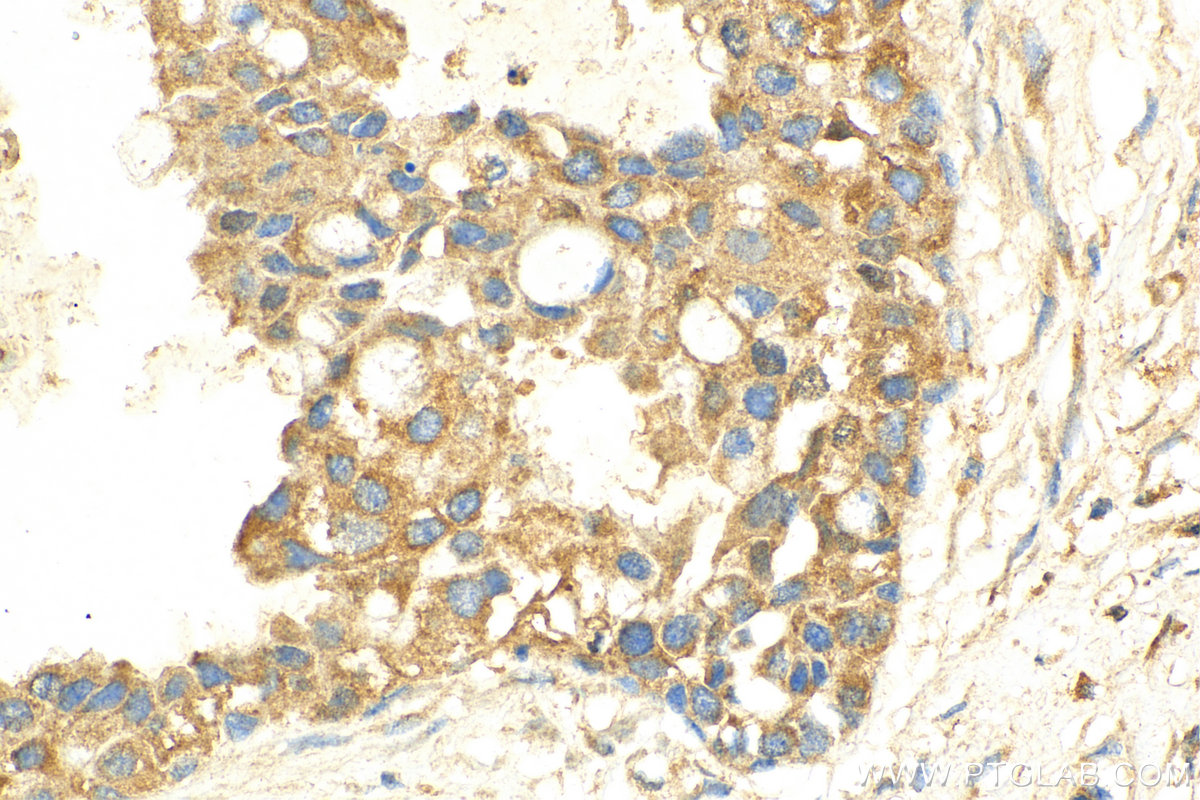

26839-1-PBS targets ADAMTS18 in IHC, Indirect ELISA applications and shows reactivity with human samples.

| 经测试应用 | IHC, Indirect ELISA Application Description |

| 经测试反应性 | human |